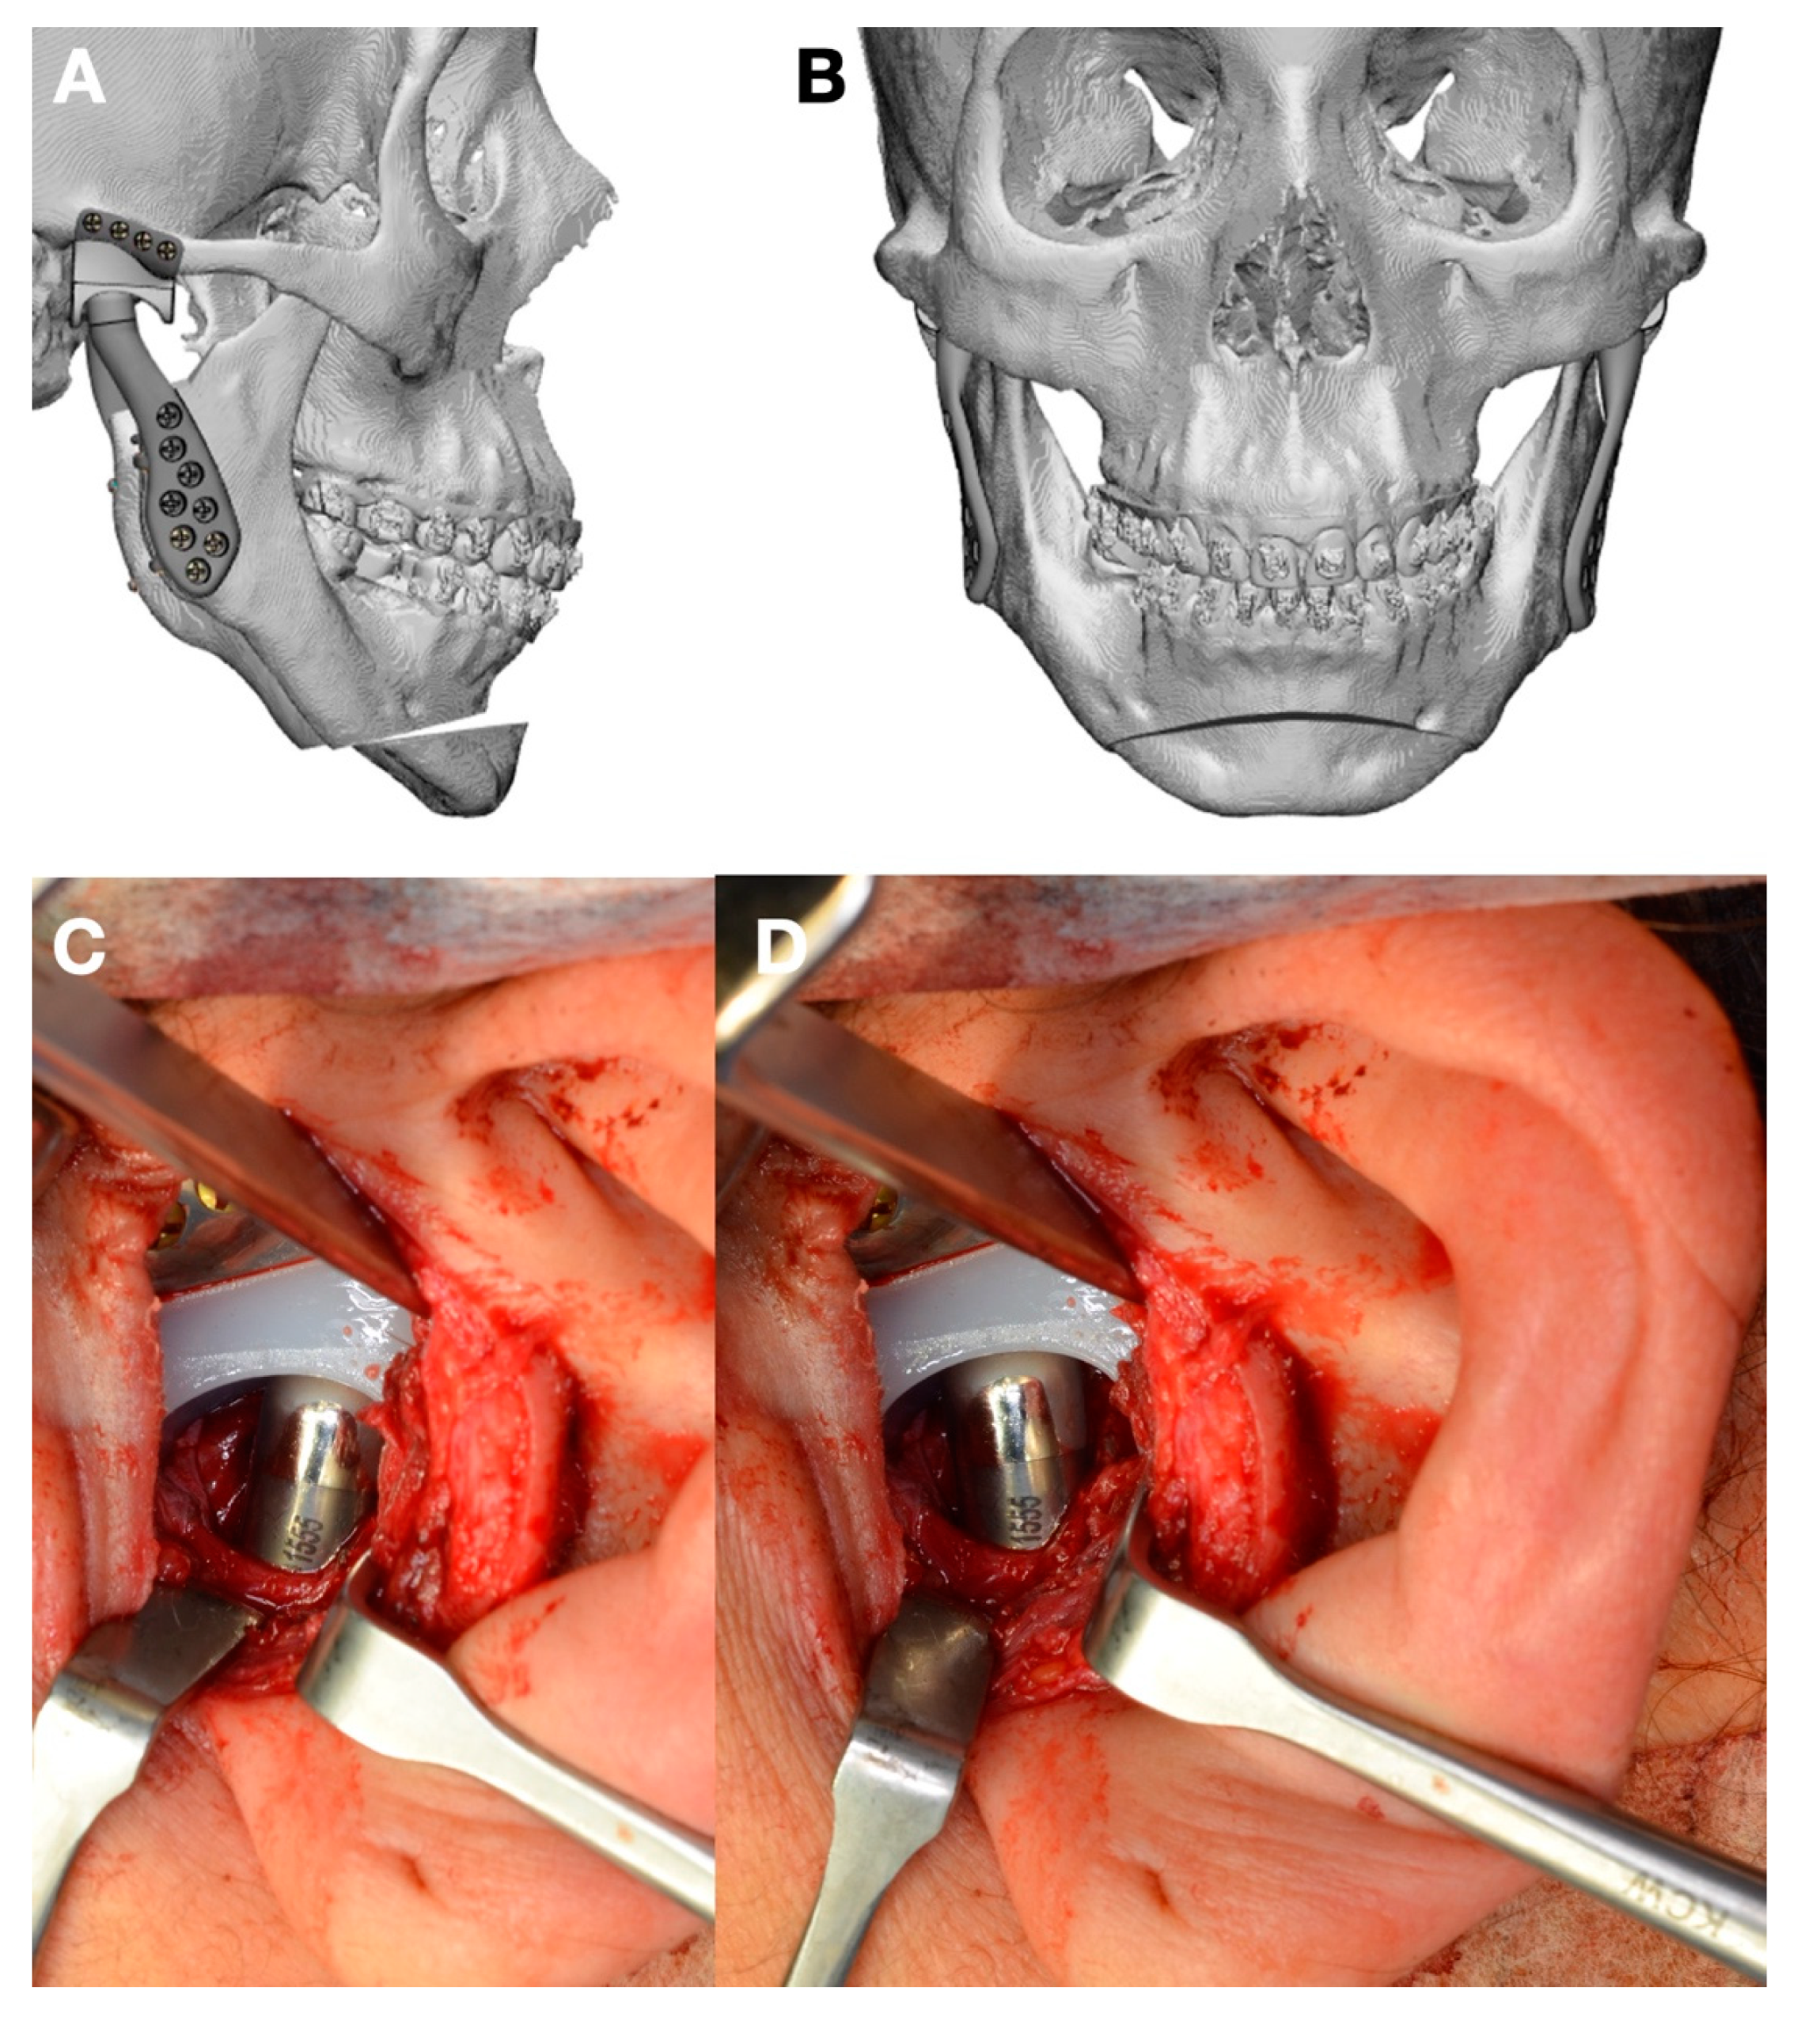

- Volume and Size Augmentation of the Mandibular Condyle

- Malformations, Pathology, or Trauma of the Mandibular Condyle